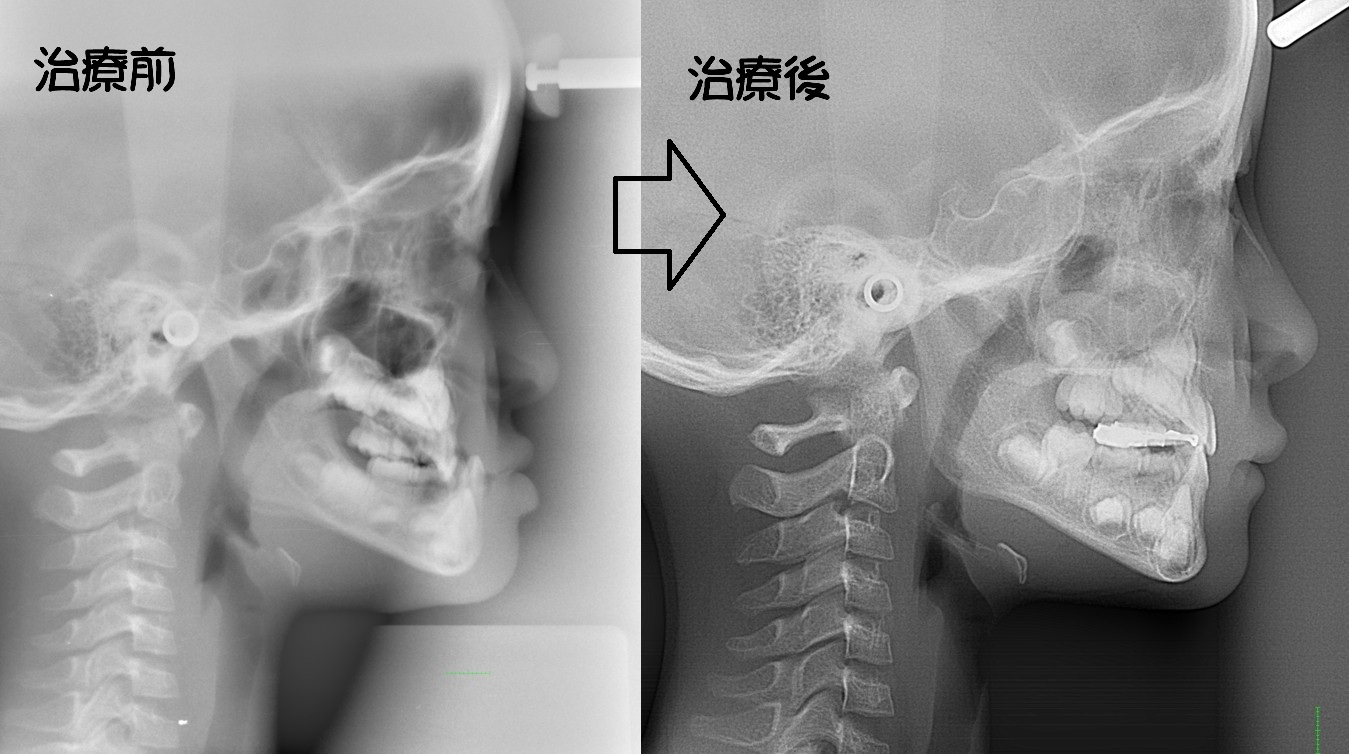

顎変形症

骨格性反対咬合・骨格性上顎前突・骨格性開咬・骨格性下顎側方偏位 などの外科矯正手術を必要とするもの

外見の改善を重要視するならば、矯正治療と外科処置を併用することにより適切な噛み合わせを回復したほうがよい場合もあります。

・主訴:下あごが出ている

・診断:骨格性下顎前突

・年齢:27歳

・使用した主な装置:マルチブラケット装置

・抜歯部位:なし

・治療期間:30か月

・通院回数:36回

・費用の目安:保険適応。保険矯正代金は、20万円くらい。症状・期間によってかわります。

・その他大学病院で外科矯正手術代金がかかります。